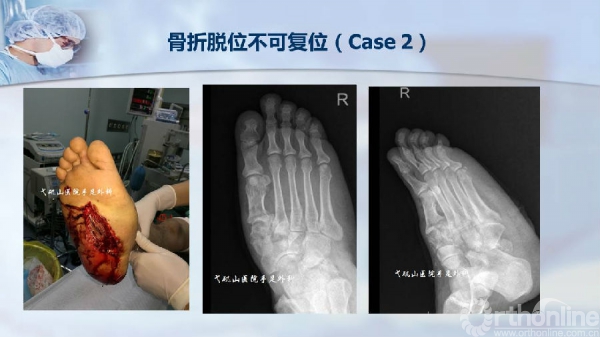

2017-06-21 文章来源:皖医弋矶山医院 作者: 夏江 我要说